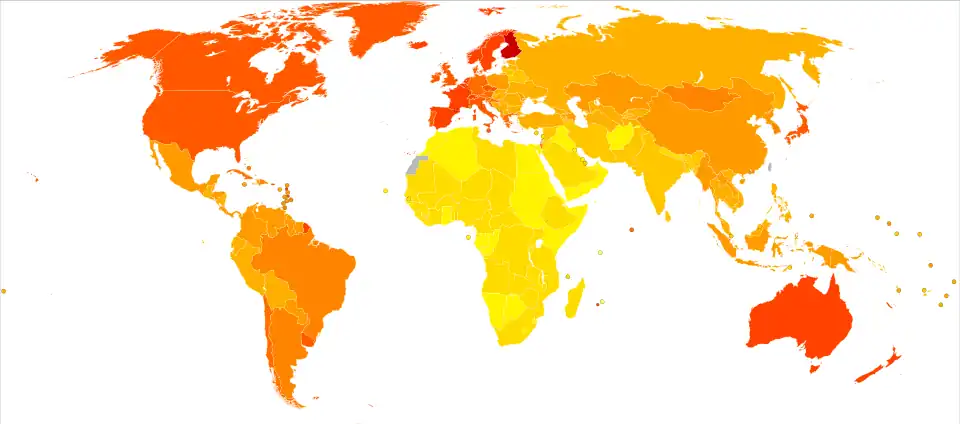

Prognóstico

| Sem dados ≤ 50 50–70 70–90 90–110 110–130 130–150 | 150–170 170–190 190–210 210–230 230–250 ≥ 250 |

As duas principais medidas usadas em estudos epidemiológicos sobre Alzheimer são a incidência e a prevalência. A incidência é o número de novos casos por cada unidade de pessoa-tempo em risco; geralmente, o número de novos casos por cada milhar de pessoas-ano. A prevalência é o número total de casos da doença em determinada população a dado momento. No que diz respeito à incidência, os estudos longitudinais coorte (estudos onde a população sem a doença é seguida ao longo dos anos) mostram taxas de incidência entre 10 a 15 por cada mil pessoas-ano para todas as demências e entre 5-8 para os casos específicos de Alzheimer, o que significa que mais de metade de todos os novos casos anuais de demência são Alzheimer.[217][218] A idade avançada é o principal fator de risco da doença, pelo que a taxa de incidência não é igual em todas as idades: por cada cinco anos após os 65 anos, o risco de adquirir a doença duplica, em média.[217][218] Existem também diferenças entre os sexos na taxa de incidência, uma vez que as mulheres apresentam maior risco de desenvolver Alzheimer, principalmente acima dos 85 anos.[218][219] Existe uma relação inversamente proporcional entre a prevalência de demência e a escolaridade. Nos indivíduos com oito anos ou mais de escolaridade a prevalência é de 3,5%, enquanto que nos analfabetos é de 12,2%.[220]

A prevalência de Alzheimer em determinada população depende de diversos fatores, entre os quais a incidência e a taxa de sobrevivência. Uma vez que a incidência de Alzheimer aumenta com a idade, é especialmente importante considerar a média de idades da população a estudar. Em Portugal e durante o ano de 2009, a Alzheimer Europe estima que existam cerca de 153 000 pessoas com demência, das quais 90 000 com Alzheimer.[221] No Brasil, em 2009, o número total de casos era de cerca de um milhão.[222] Nos Estados Unidos, segundo dados de 2000, estima-se que a prevalência seja de 1,6% no intervalo entre os 65 e 74 anos, aumentando para 19% no intervalo de 75-84 e para 42% no intervalo superior a 84 anos.[223][224] Em regiões menos desenvolvidas, as taxas de prevalência são inferiores.[225] A Organização Mundial de Saúde estima que em 2005 0,379% das pessoas em todo o mundo tivessem demência, número que aumentará para 0,441% em 2015 e para 0,556% em 2030,[226] conclusões que são confirmadas por outros estudos.[225] Outro estudo estimou que em 2006 0,4% da população mundial (intervalo entre 0,17–0,89%) fosse atingida por Alzheimer, o que corresponde a um número absoluto de 26,6 milhões (intervalo 11,4–59,4 milhões). Estima-se também que em 2050 a taxa de prevalência será três vezes superior e o número absoluto de casos quatro vezes superior.[227][228]